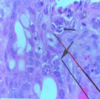

AVIAN COCCIDIA

Nucleus pressed by side

- Schizogony

- Gametogony

AVIAN COCCIDIA

- Gametogony

- Scchizogony